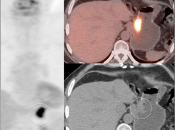

• The utility of PET/CT lies in its assessment of regional nodes and distant metastatic disease.

• Distant Disease: Most commonly to the liver, peritoneum, lung and bone.